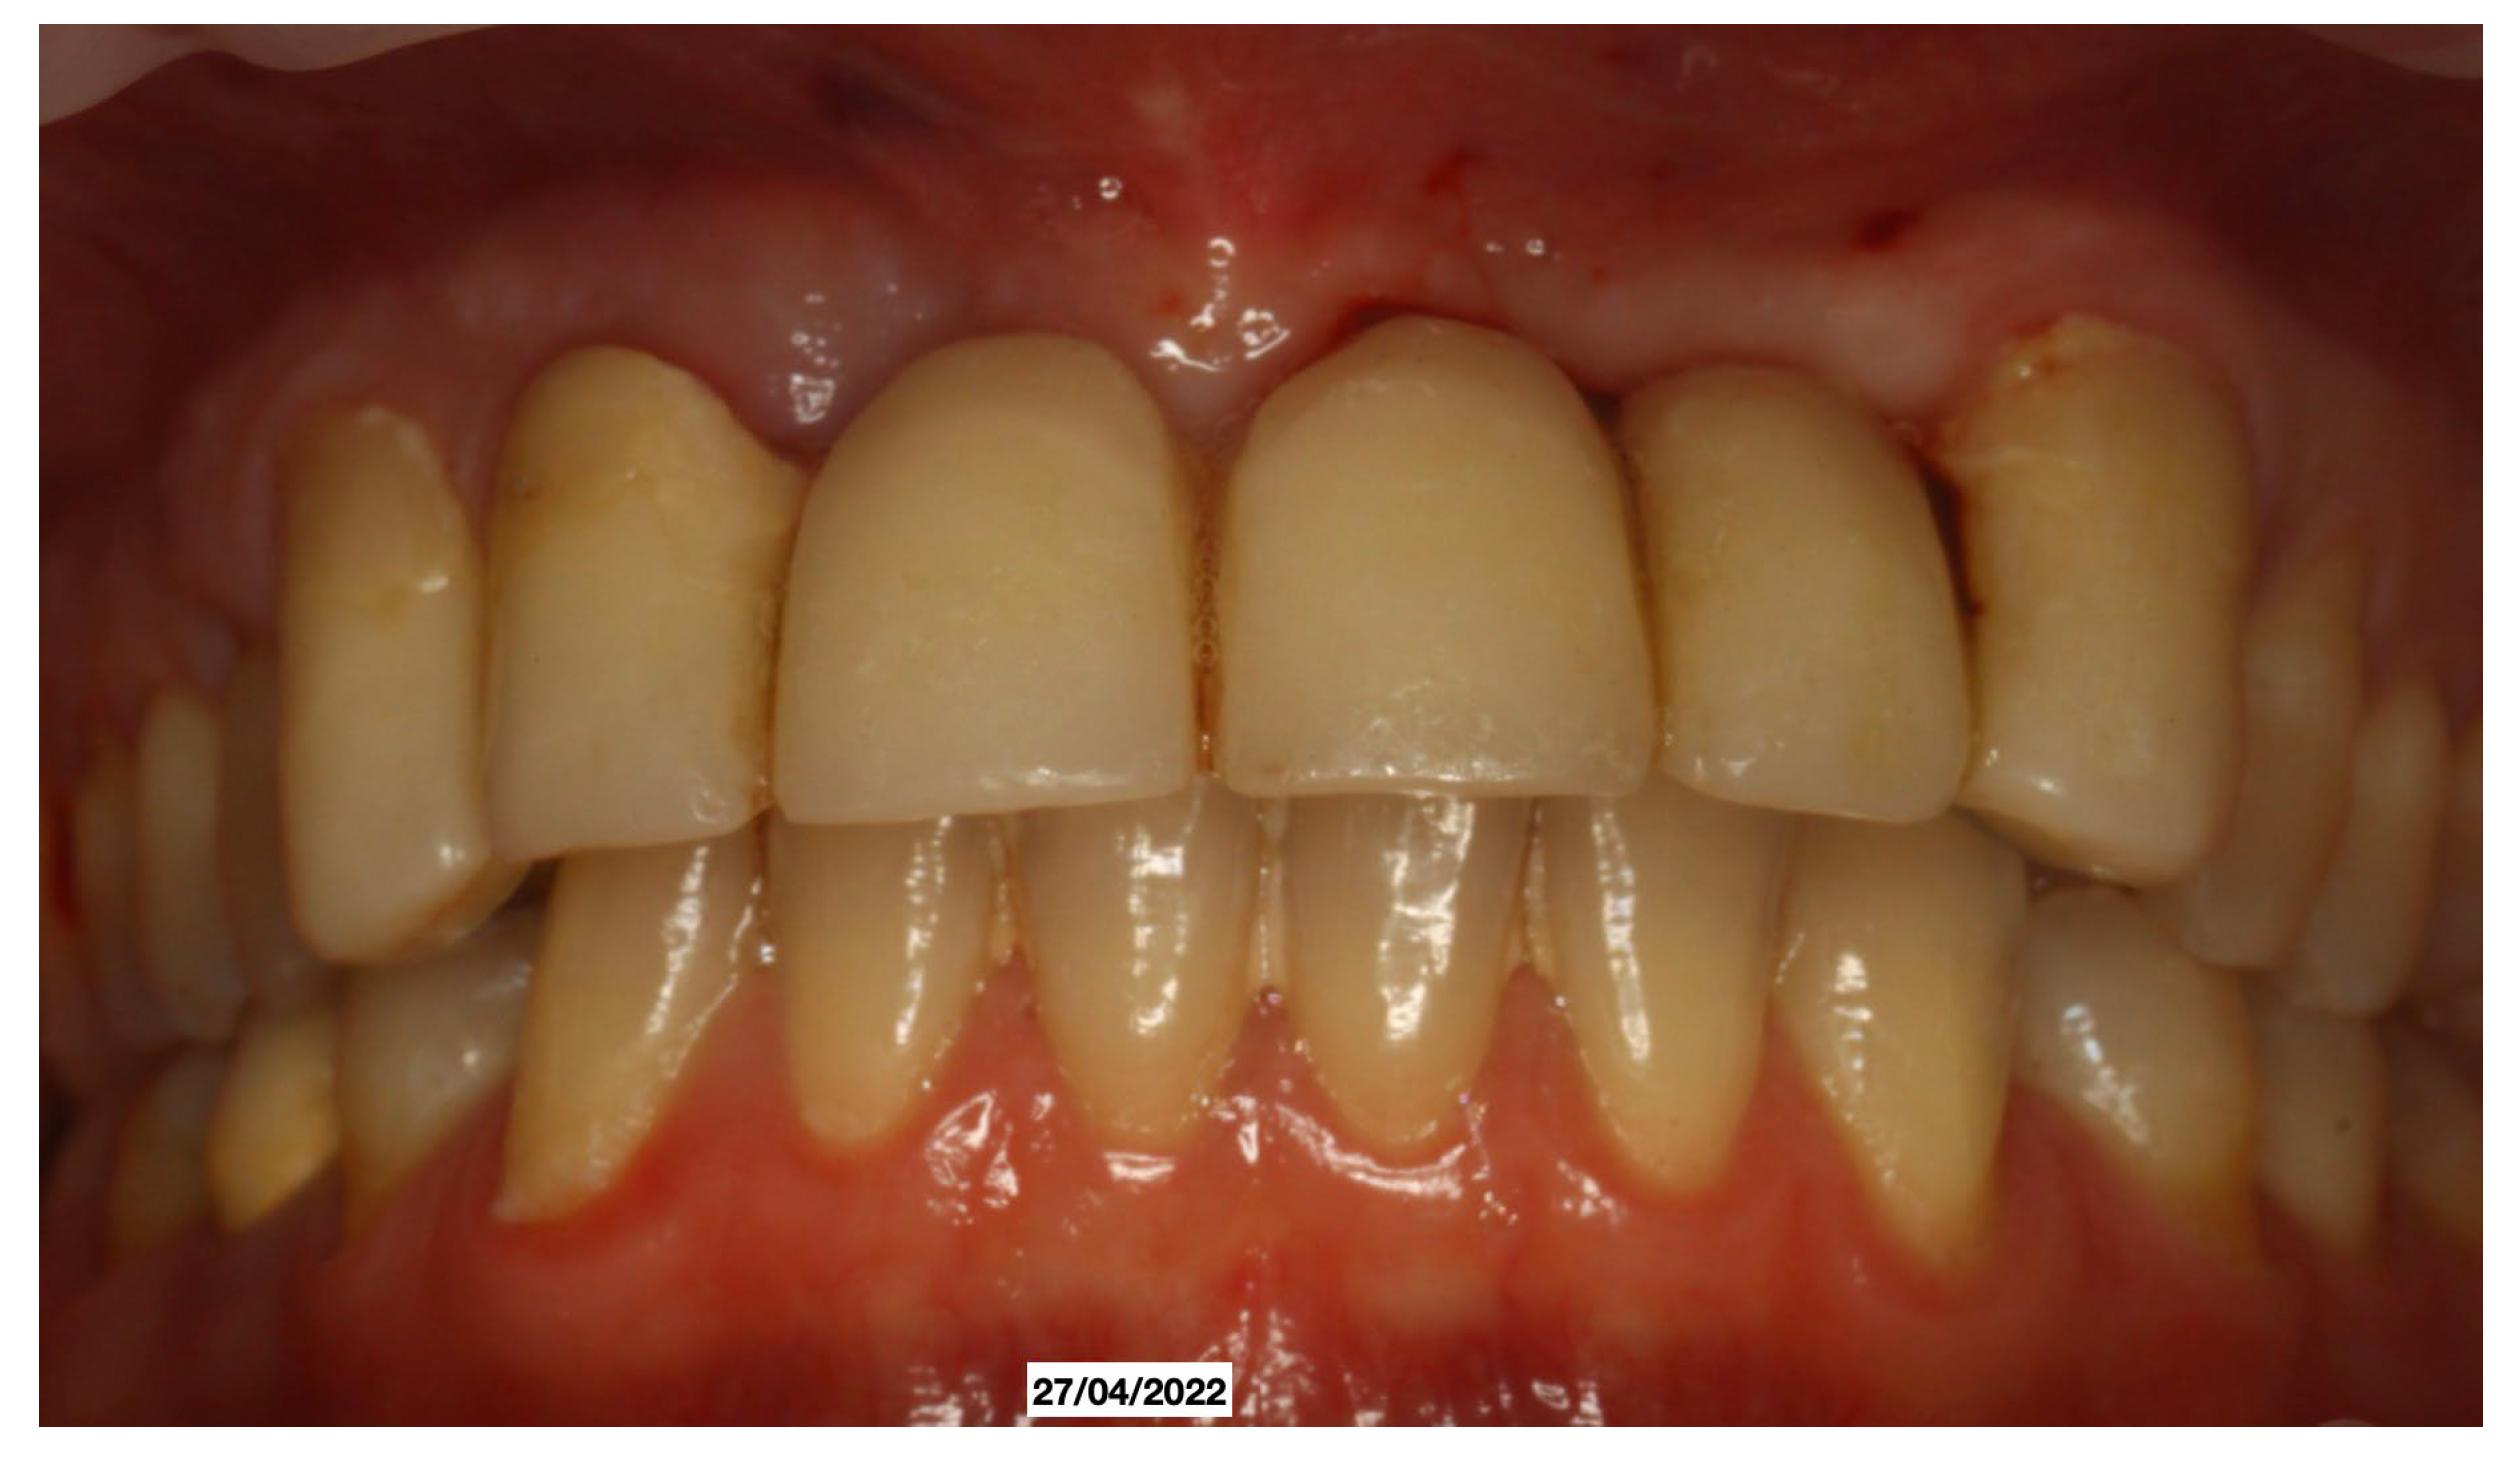

It was decided to temporarily rehabilitate the edentulism with a fixed partial denture after preparing 23-12-13 (Figure 4), keeping the adjacent teeth under observation but with a slight radiolucency already present.

Figure 4. Fixed partial denture after preparing 23-12-13.